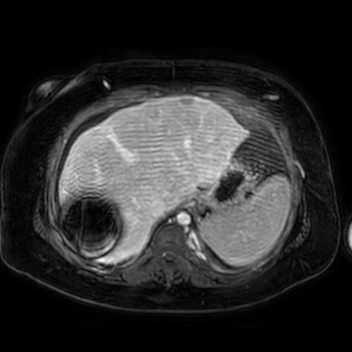

Case 2

69 M with PMH of HCV cirrhosis & HCC s/p resection in 14 years ago presenting today for a screening ultrasound.

135/73 mmHg / 78 bpm / 16 breaths/min / 96.4°F

sclerae anicteric, no jaundice

CMP wnl, AFP 5